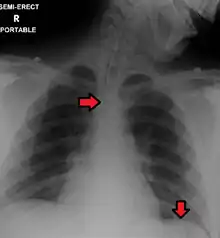

Top Arrow: Endotracheal tube Bottom Arrow: Nasogastric tube

Confirming placement

It is necessary to confirm placement of the endotracheal tube to ensure that the tube is properly positioned within the trachea and has not accidentally passed into the esophagus instead. Additionally, it is important to confirm that the endotracheal tube was not placed too deep in the trachea where is may only be ventilating one of the lungs due to it being positioned within a mainstem bronchi (frequently the right mainstem bronchi due to a more obtuse angle than the left). The gold standard for confirming successful placement of an endotracheal tube is direct visualization of the tube passing through the vocal cords and positive end-tidal carbon dioxide on capnography. Secondary methods of confirmation include oxygen saturation, chest x-ray, ultrasound, condensation in the endotracheal tube, equal chest rise, breath sounds heard on both sides of the chest (often with the assistance of a large tidal volume breath), and an absence of breath sounds over the epigastrium. No single method of confirming placement is 100% reliable so multiple methods of confirmation should be utilized.[6][13][14]